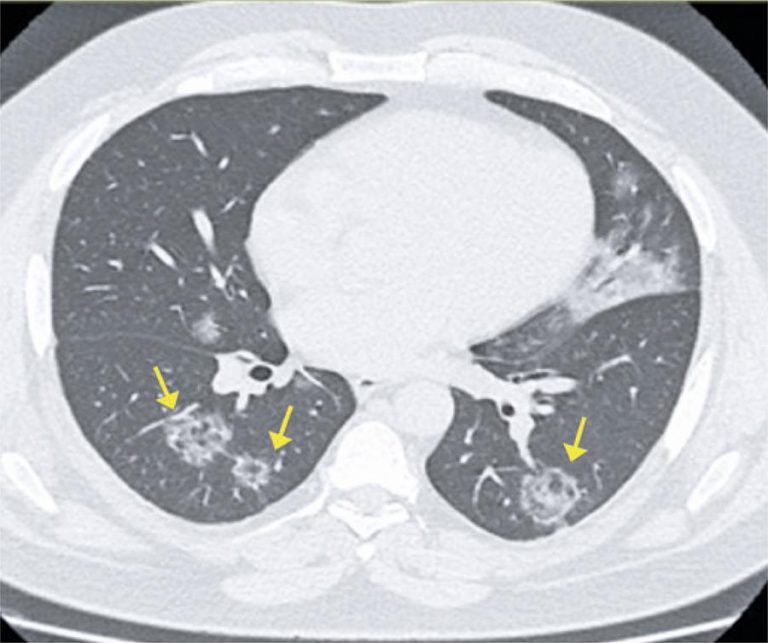

COVID-19 findings identified in chest computed tomography: a pictorial essay

The disease caused by the new coronavirus, or COVID-19, has been recently described and became a health issue worldwide. Its diagnosis of certainty is given by polymerase chain reaction. High-resolution computed tomography, however, is useful in the current context of pandemic, especially for the most severe cases, in assessing disease extent, possible differential diagnoses and searching complications. In patients with suspected clinical symptoms and typical imaging findings, in which there is still no laboratory test result, or polymerase chain reaction is not available, the role of this test is still discussed. In addition, it is important to note that part of the patients present false-negative laboratory tests, especially in initial cases, which can delay isolation, favoring the spread of the disease. Thus, knowledge about the COVID-19 and its imaging manifestations is extremely relevant for all physicians involved in the patient care, clinicians or radiologists.